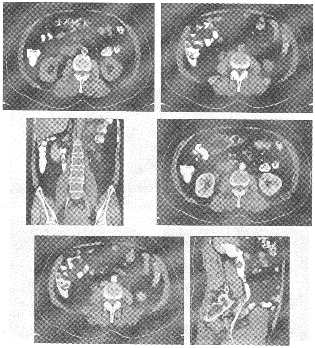

男,61岁,无痛性血尿1月余,加重3天。

如图所示,应首先考虑哪种疾病 YZ114_366_19_3.gif

• A.肾癌

• B.肾盂移行细胞癌

• C.肾盂平滑肌瘤

• D.息肉

• E.阴性结石

• F.先天变异

诊断依据是

• A.老年人

• B.肾盂充盈缺损

• C.输尿管上端充盈缺损

• D.宽基底充盈缺损肿块

• E.肾盂积水

• F.全程无痛性血尿